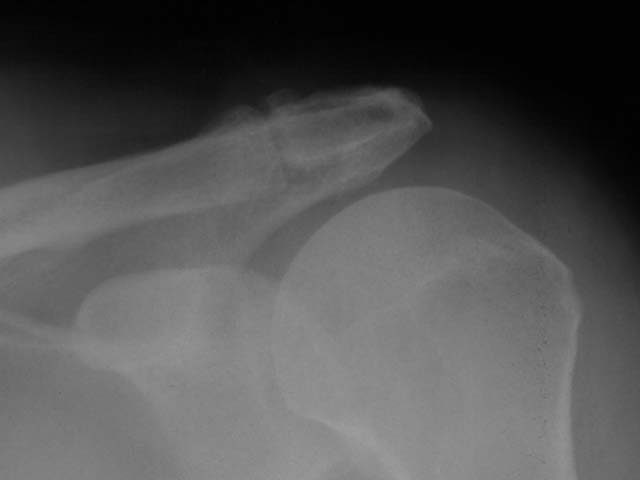

To provide an opportunity for the comparison of image scanning techniques, we are posting in the "Digital Images" forum of the HWB Home Page (http://www.hwbf.org/hwb/) an AP Shoulder film scanned with a $16,000 Howtek Scanmaster DX Xray scanner and a $200 "Snappy" video digitizer. The "Snappy" plugs into the video port of a camcorder or VCR. JPEG compression of either 5:1 or 10:1 are applied to the scans. We would be interested in any feedback with respect to the diagnostic quality of these images.

Click images to enlarge.ROW 1: JPEG 5:1 compression

4)